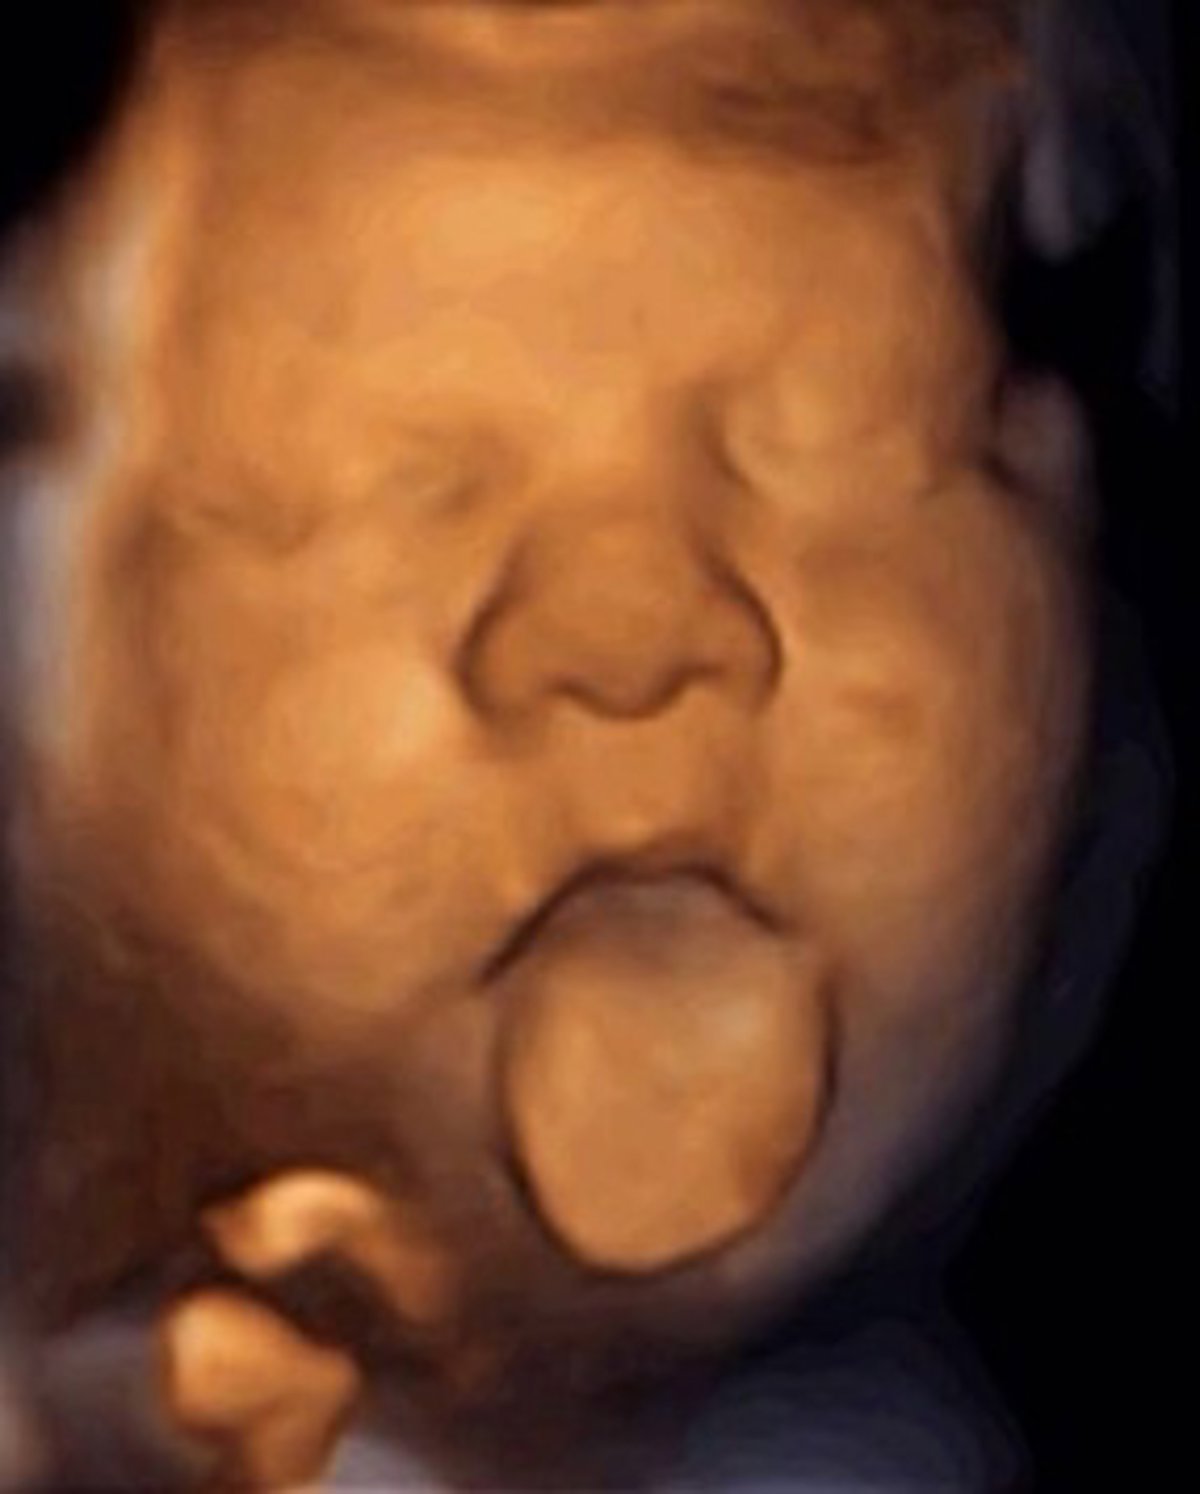

Los fetos de más de 16 semanas y que miden al menos 11 centímetros mueven la boca de forma exagerada cuando escuchan la voz materna o una voz humana, llegada a través de un dispositivo intravaginal desarrollado con este objetivo, ha informado el Institut Marquès de Barcelona este miércoles en un comunicado.

Para estudiar las reacciones de los fetos se ha utilizado el dispositivo 'Babypod', que se introduce en la vagina como un tampón, se conecta al móvil y permite hacer llegar al feto la voz de la madre o de cualquier otra persona.

Después de constatar que el 70% de los fetos mueven solo la boca cuando se les habla y en cambio cuando escuchan música realizan movimientos más complejos, ahora se plantean estudiar si "los centenares de fetos que han sido estimulados durante la gestación, cuando nazcan serán capaces de reconocer la voz de sus padres", ha explicado el investigador.

Además, el nuevo reproductor de sonido también permite descartar la sordera fetal y facilita hacer las ecografías al provocar una respuesta en el bebé y así mejorar la visión de las estructuras fetales.